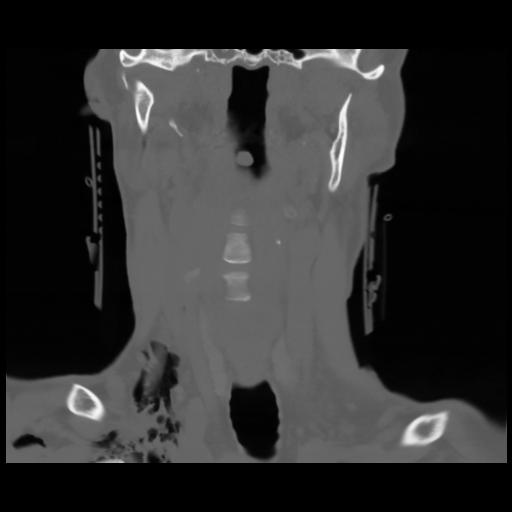

13 P.BLANDAS,,Coronal,2.000,P.BLANDAS,Coronal,